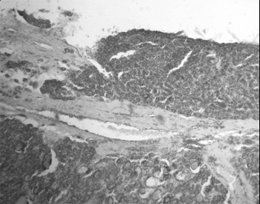

Mногофакторный анализ нашего материала показал, что мультицентричность опухоли как самостоятельный фактор на прогноз у больных с дифференцированными карциномами не влиял. Не выявлено каких-либо отличий в прогнозе при ангиоинвазивных и неангиоинвазивных формах дифференцированных карцином. При экстратиреоидной инвазии высокодифференцированной карциномы летальный исход у больных был выше, чем при очаговой инвазии в капсулу железы (рис.1).

Рисунок 1. Широкий инвазивный рост в фиброзную капсулу при фолликулярном раке щитовидной железы с экстратиреоидным распространением. Окраска гематоксилином и эозином. X 400.